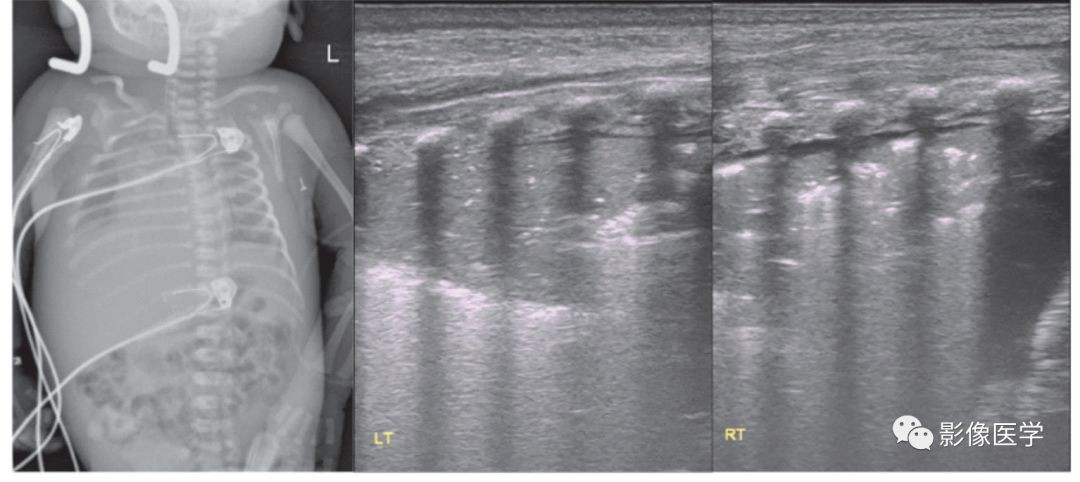

图 6-2 重症感染性肺炎(1)

胎龄38+2周,剖宫产分娩,出生体重3 420g。因呼吸困难3d于出生后20d入院。体温38℃,双肺可闻及密集细湿啰音。血常规:WBC 22×109/L,N 78%,单核细胞比例12.2%,CRP 66.8mg/L。胸部X线检查结果符合新生儿肺炎改变。肺脏超声显示双肺边缘不规则的大面积实变区伴支气管充气征,胸膜线模糊或消失,A线消失。